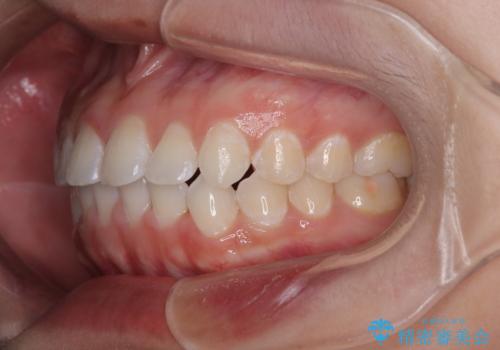

- 上下前歯のデコボコを気にして来院された患者様です。

ワイヤー矯正でもマウスピース矯正でも可能でしたが、短期間で、自身の手を煩わせることなく治療を行いたいとのことで、ワイヤー装置にて矯正治療を行うこととしました。

僅か半年強、あっという間に治療を終えることができました。